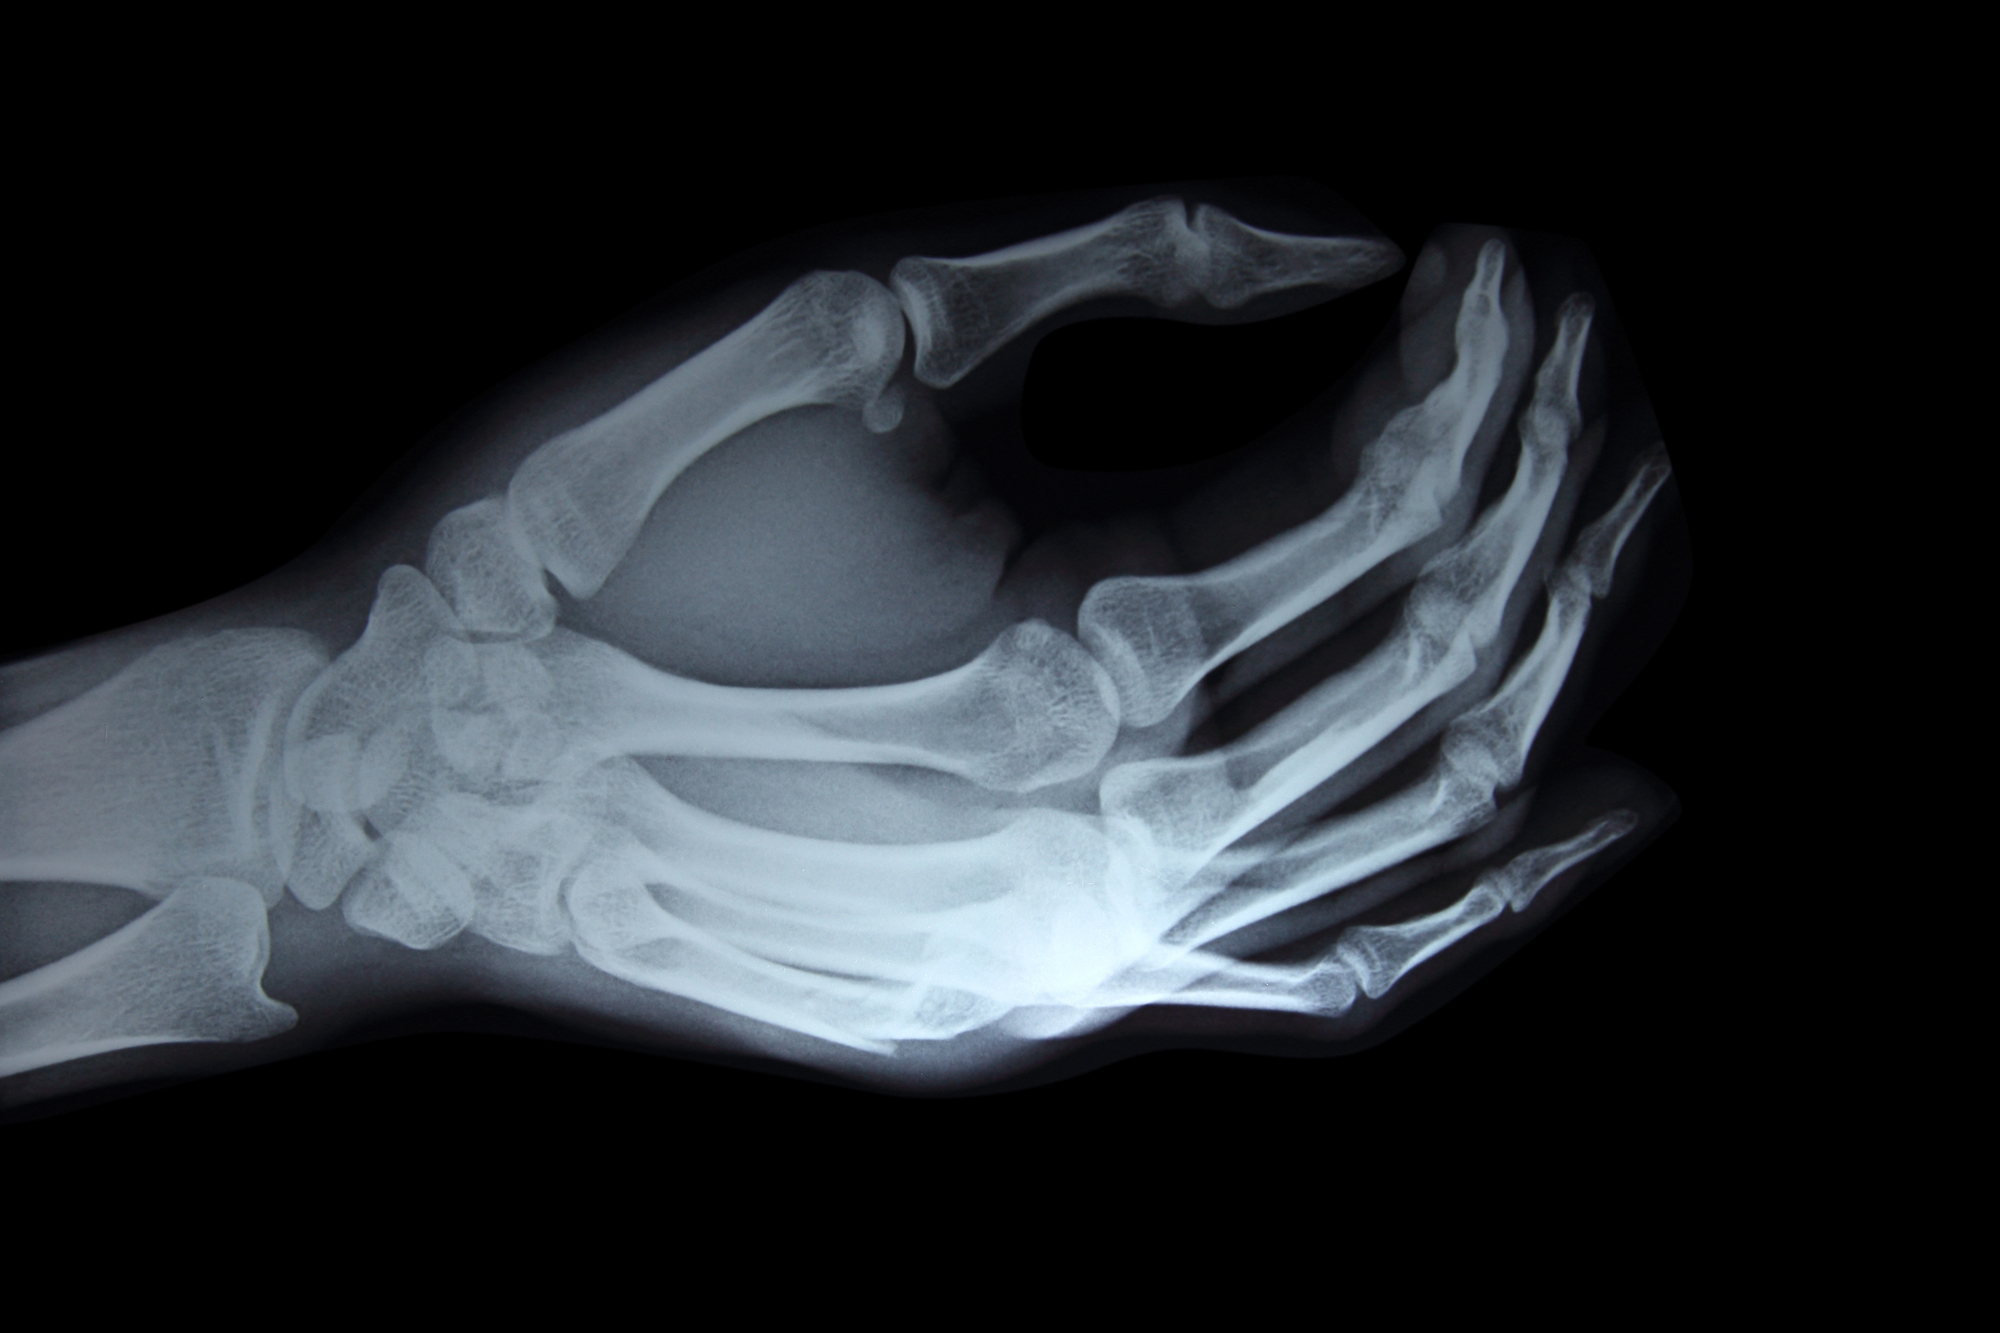

2024년 5월 27일, 삼성전자 기흥캠퍼스에서 반도체 원재료인 웨이퍼 검사 장비를 점검하던 중 두 명의 노동자가 방사선에 피폭되는 사고가 발생했습니다. 이 중 한 명은 피폭 다음 날 부터 손이 붓기 시작했습니다. 현재는 손가락 괴사로 치료 중이며, 절단을 해야 할지도 모르는 상황이라고 보도되었습니다. 사고의 원인은 방사선 자동 차단 기능을 담당하는 인터록 장치가 제대로 작동하지 않았기 때문입니다. 방사선 노출 시간은 수초 간의 짧은 시간이었다고 알려졌습니다.

피부방사선손상위 사고에서 방사선에 피폭된 노동자들은 손에 국한하여 방사선에 피폭되었습니다. 따라서 피부방사선손상(Cutaneous Radiation Injury, CRI)에 해당합니다. CRI는 높은 수준의 방사선에 급성 노출되었을 때, 피부와 그 아래 조직에 발생하는 손상입니다. 전신에 노출되는 급성 방사선 증후군(Acute radiation syndrome, ARS)도 일반적으로 피부 손상을 동반하지만, CRI는 ARS 증상이 없어도 발생할 수 있습니다.

1. 전조기: 노출 후 몇 시간 이내에 홍반, 열감, 가려움 등이 나타나며, 1~2일 정도 지속됩니다.2. 잠복기: 증상이 사라지는 기간으로, 통상적으로 1~2주 정도입니다. 손과 발바닥 부위는 상대적으로 길어지고, 피폭량이 크면 짧아집니다.3. 증상기: 노출 후 며칠부터 몇 주 사이에 다시 홍반, 열감, 부종이 생깁니다. 심각한 경우 궤양과 괴사까지 진행합니다.4. 후기 효과: 노출 후 몇 개월에서 몇 년간 진피 위축, 궤양 재발, 진피 괴사, 기형, 모세혈관 확장증, 섬유증, 혈관염, 색소 변화, 통증 등이 나타나며, 피부암이 발생할 수 있습니다.

피폭량에 따른 피부의 변화2Gy-15Gy

전조기가 1~2일 정도이거나 나타나지 않을 수도 있음잠복기는 2~5주 정도잠복기 후 20~30일 정도에 피부 발적, 부종, 색소 침착이 나타나고, 건조 탈피 후 완전히 회복*피부증상과 흡수선량 역치

- 잠복기 이후 홍반 발생: 3 Gy

- 일시적 탈모: 3 Gy

- 영구적 탈모: 7 Gy

- 건성 박리: 10 Gy

- 습성 박리: 15 Gy

- 피부 괴사: ≥25 Gy

15Gy-40Gy노출 후 6~24시간 사이 전조기가 나타남잠복기는 1~3주 정도증상기에는 홍반, 열감, 부종, 피부의 갈색 변화가 나타남증상이 좋아졌다가 다시 나타나며, 궤양이 발생노출 후 최대 10년 동안 모세혈관 확장증이 나타남.40 Gy 이상

노출 후 4~24시간 내 통증, 따끔거림이 나타남전조기는 없거나 2주 미만증상기에는 침식과 궤양, 심한 통증이 생김증상이 좋아졌다가 다시 발생하며, 새로운 궤양이 생김궤양은 괴사가 진행될 수 있고, 완전히 치유되기까지 몇 달에서 몇 년이 걸림550Gy 이상노출 후 몇 분에서 몇 시간 만에 바로 증상이 나타남

서울반도체, 삼성전자 피폭사고 사례에서 노출수준

서울반도체 피폭사고의 경우 대부분 회복되어서, 노출량이 25 Sv 미만이었을 것으로 추정됩니다. 다만, 추후 피부암이 발생할 위험이 증가합니다.

이번 삼성전자 사고에서 2명의 노출량은 각각 28 Sv, 94 Sv였는데, 94 Sv에 노출된 노동자는 피부괴사가 반복적으로 발생하면서 피부이식이나 절단을 고려해야할 상황이라고 합니다.